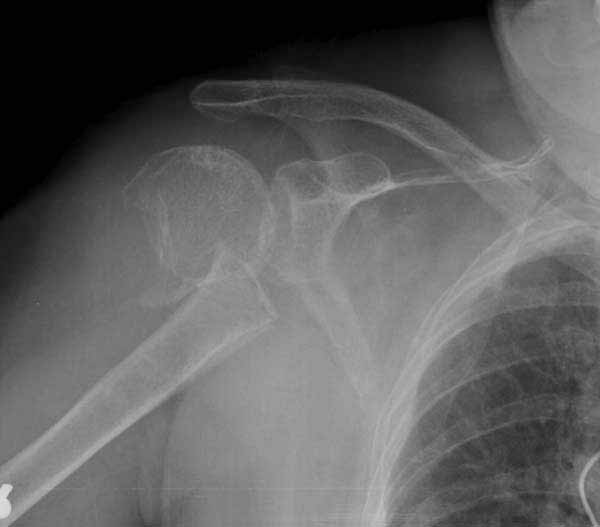

Здесь результат похожего случая, больная 87 лет, отягощенная сердечными делами и два года назад установка pacemaker и нескольких стентов. На третий день, сегодня утром сделали операцию. Послеоперационный псевдовывих связанный с релаксацией мышц и общим обезболиванием.